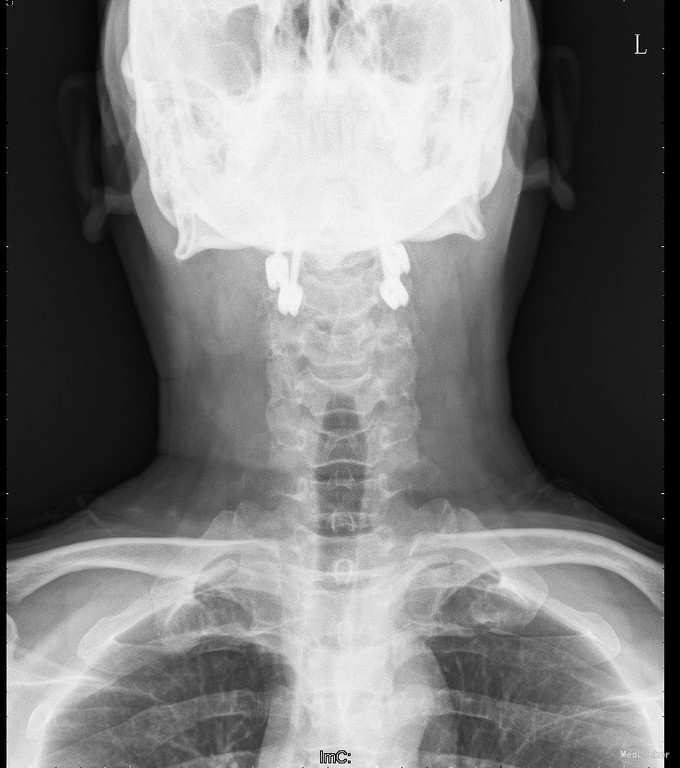

查体:查体:T:36.7oC,P:80次/分,R:20次/分,BP:137/82mmHg。神志清楚,无病容,皮肤巩膜无黄染,全身浅表淋巴结未见肿大。。颈静脉正常。心界正常,心律齐,各瓣膜区未闻及杂音。胸廓未见异常,双肺叩诊呈清音,双肺呼吸音清,未闻及干湿啰音及胸膜摩擦音。腹部外形正常,全腹柔软,无压痛及反跳痛,腹部未触及包块,肝脏肋下未触及,脾脏肋下未触及,双肾未触及。双下肢无水肿。视:平车推入病房,颈椎颈托围领固定,颈部、前额部及全身皮肤未见皮损及异常。触:颈1-4棘突及椎旁明显压痛、叩击痛,感觉正常,四肢肌张力正常。动量:颈椎活动受限,尤以旋转受限为重。双侧肱二头肌反射、肱三头肌反射、膝反射正常,双侧babinski征阴性,右侧Hoffmann征阳性、左侧阴性。 辅助检查:颈椎X线片、MRI、CT提示:寰椎椎板前弓骨折,寰枢关节旋转半脱位

诊断:1.陈旧性寰枢关节旋转脱位2.陈旧性寰椎前弓骨折 治疗:全麻下行:行经前路寰枢椎脱位切开撬拨复位+经后路寰枢椎侧块螺钉内固定、去髂骨后外侧植骨融合术